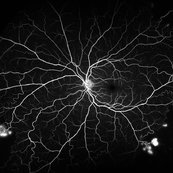

PDR with NVD and CRVO history

Dec 6 2017 by John S. King, MD

One year earlier she had a CRVO with lots of CME, treated once with avastin, and scheduled to be seen and treated a month later; at that time no nv and some cap dropout seen in FAZ area, but extent of dropout limited by heme, diffuse cme, and no wide field image at that time; lost to follow up until a year later; see above

Imaging device: Optos

Condition/keywords: central retinal vein occlusion (CRVO), diabetic retinopathy